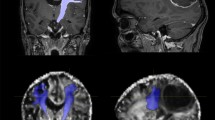

Direct coordinates, measured on the dentatorubrothalamic tract (DRTT) after DTI data postprocessing, as described below. All MRI examinations were performed on a 3 T scanner (Discovery 750w, GE Healthcare) using a 32-channel head coil before the preoperative planning procedure. DTI sequences were acquired using the following parameters: 33 diffusion directions, TR 5700 ms, TE 98 ms, parallel imaging (acceleration factor two), 3 mm slice thickness, 39 slices, matrix 128 × 128, 230 mm FOV, b value 1000 s/mm2, acquisition time 4:01 min. A T1-weighted 3D IR FSPGR BRAVO sequence with multiplanar reconstructions was also acquired (parameters: FOV 24, slice thickness 1.6 mm, flip angle 20°, prep time 450, TE 3.2, matrix 256 × 192, NEX 3, duration 13 min). Probabilistic fiber tracking was performed using a dedicated software (Brainance MD, Advantis Medical Imaging, Eindhoven, NL). EPI correction tool for distortion correction was applied before image analysis. The fractional anisotropy threshold was set at 0.15, minimum fiber length 0 mm, maximum fiber length 200 mm, angular threshold 27°, and step size 1 mm. The dentatorubrothalamic tract (DRTT) was obtained by manual definition of three regions of interest (ROIs) on axial images: the cerebellar dentate nucleus ipsilateral to the target, the ipsilateral red nucleus, and the supposed location of the ipsilateral Vim at the level of the thalamus on the AC-PC plane (Fig. 2).

Figure 2 DTI tractography of the dentatorubrothalamic tract (DRTT). Manual definition of three regions of interest (ROIs) on axial images: the cerebellar dentate nucleus ipsilateral to the target (a1), the ipsilateral red nucleus (a2), and the supposed location of the ipsilateral Vim at the level of the thalamus on the AC-PC plane (a3). Fiber tractography 3D (b) and multiplanar 2D (c) visualization of the DRTT.

After DRTT reconstruction, direct coordinates were measured: (i) the mediolateral (RL) coordinate, defined as the distance from the center of the fiber tract to the AC-PC midline on the axial slice; (ii) the anteroposterior (AP) coordinate, defined as the distance from the PC line to the point where the RL coordinate intersected the AC-PC line on the axial slice; (iii) the superoinferior (SI) coordinate, defined as the distance from the center of the fiber tract to the plane passing through the AC-PC line on the coronal slice (Fig. 3).

Direct AP (a), RL (b) and SI (c) coordinates manual measurement on multiplanar 2D reconstruction of the DRTT.